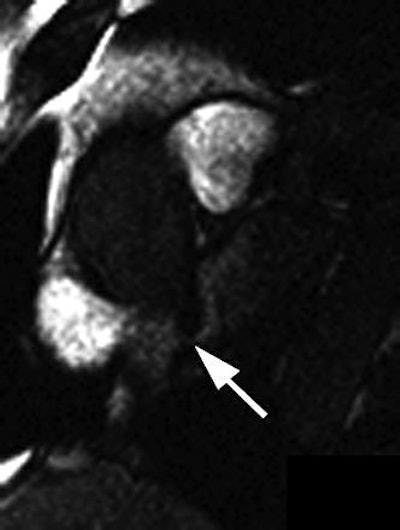

| Thirty-two-year-old man with PFO grade 3 on TEE and grade 3 on MRI. Above and below, images show enhancement of entire left atrium due to right-to-left-shunting (arrows) before enhancement of pulmonary vein. Mohrs OK, Petersen SE, Erkapic D, Rubel C, Schräder R, Nowak B, Fach WA, Kauczor HU, Voigtlaender T, "Diagnosis of Patent Foramen Ovale Using Contrast-Enhanced Dynamic MRI: A Pilot Study" (AJR 2005; 184:234-240). |

The results showed that PFO was visually identified in all 15 patients, and excluded in the control group on MRI. For the patients with PFO, "an early contrast enhancement due to intracardiac right-to-left shunting was present in the left atrium before the contrast agent reached the pulmonary veins," the authors wrote. There was a 20% prevalence of atrial septal aneurysm in the PFO population, and MRI correctly identified these cases.

Using the signal-time curves, all PFO patients showed curves with an early first peak in the left atrium of 160% of baseline signal at seven seconds, followed by the peak in the pulmonary vein of 486% at 17 seconds.